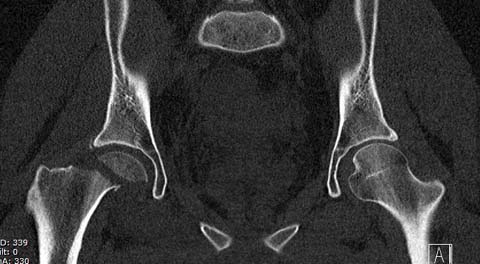

Уважаемые коллеги добрый вечер! Хотелось бы узнать ваше мнение о возможных ранних сроках наступления асептического некроза или коксартроза при данном виде оперативного лечения, может кто-то уже оперировал данную патологию и есть наблюдения. Случай практически идентичный описанный в январе 2015 на ортофоруме Никитой Николаевичем Заднепровским. Молодой человек 20 лет ДТП 23.02.2015, Диагноз: Сочетанная травма. Закрытый переломо-вывих головки и перелом заднего края вертлужной впадины (Pipkin4) правой бедренной кости. Открытый подтаранный вывих правой стопы. При поступлении в ЦРБ вправление вывиха головки бедра и подтаранного вывиха стопы.

Далее перевод к нам в Травмоцентр и 03.03.2015. через 8 дней операция, выполнен остеосинтез головки 3-мя самокомпрессирующими винтами Autofix под разными углами с погружением в субхондральный слой. Доступ Kocher-Langenbeck с флип-остеотомией большого вертела и задним хирургическим вывихом головки бедра. В полости сустава два свободно-лежачих фрагмента хряща головки, которые были удалены. На снимках виден дефект хряща головки после репозиции. Небольшой фрагмент заднего края фиксирован двумя спонгиозными винтами. Далее шов раны с дренированием. На 2 сутки пациент поворачивался на здоровый бок с валиком между ног, на 4 сутки сидел в кровати и на 6 сутки ходил с помощью костылей.

КТ после вправления - это последнее?

На мой взгляд, развитие артроза и AVN в большей степени зависит от давности вывиха и качества оперативной техники. Хирургический вывих бедра- не самая простая процедура и с подводными камнями, в остеосинтезе из переднего доступа тоже есть проблемы.

Здесь значимый задний край с подвывихом бедра кзади и острым краем вертлуги - задний доступ с вывихом и синтезом заднего края винтами и пластиной

Здесь клинические примеры: Первый случай передний доступ, второй с ICP monitor Flipp Trochanteris

и с переломом заднего края.